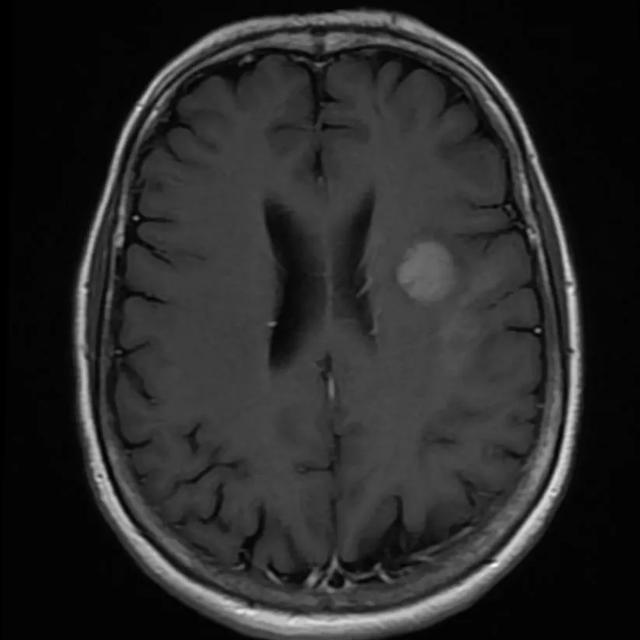

En MR-scanner kan lave et detaljeret billede af kroppens indre ved hjælp af et kraftigt magnetfelt, som registreres af en computer. Magnetfeltet er så kraftigt, at du ikke må have metaldele i kroppen. Det gælder dog ikke plomber i tænderne.

En MR-scanning viser betydeligt flere detaljer end CT-scanning, og hjernen kan ses fra alle vinkler ved denne undersøgelse. Læs mere om undersøgelsen:

Scanningsbilledet kan være en god hjælp til at forstå sin sygdom. Nogle patienter får et enkelt epileptisk anfald som det første symptom, og de kan have svært ved at tro på, at de har en hjernetumor.